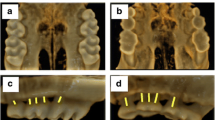

Rapamycin trough blood levels in the RAPA group were 22.3 ± 2.1 ng/ml. As shown in Table 1, these animals exhibited marked growth impairment, as demonstrated by reductions in weight gain, nose to tail-tip length, and longitudinal bone growth rate when compared with control animals. Significant decreases in food intake and food efficiency were also observed in RAPA animals when compared with C animals. Representative images of tibial growth-plate sections illustrating the differences in longitudinal bone growth rate are shown in Fig. 1.

Representative sections of proximal tibial growth plates of control (C; a) and rapamycin-treated (RAPA; b) rats. The mean distance between the metaphyseal end of the growth plate and the fluorescent calcein front indicates longitudinal bone growth rate during the last 3 days of the study. Magnification bars: 100 μm